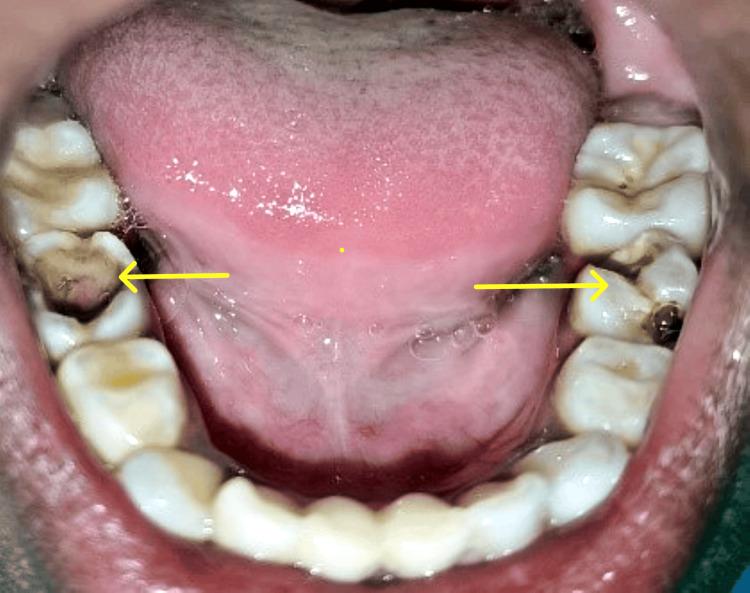

Oral health is a vital part of overall health, particularly for children with special healthcare requirements. The terms "dumb" and "mute" are frequently linked with the term "deaf" due to the connection between hearing loss and speech impairment. A hearing and speech-impaired child may be unable to express completely because of the communication barriers. It is important to treat special children with utmost care and safety. This case report describes the dental management of an 8-year-old special child reported with multiple carious lesions under general anesthesia as she was not well acquainted with sign language. In a hospital setting under general anesthesia (GA), all necessary treatments are carried out in a single appointment. Since it is monitored by a multi-disciplinary team it can safely provide effective care to a child with hearing impairment and mutism.

口腔健康是整体健康的重要组成部分,对于有特殊医疗需求的儿童尤为如此。由于听力丧失与言语障碍之间的关联,“哑巴”和“缄默”这两个词经常与“聋”这个词联系在一起。有听力和言语障碍的儿童可能由于沟通障碍而无法完全表达自己。以最大程度的关怀和安全对待特殊儿童非常重要。本病例报告描述了一名8岁特殊儿童的牙科治疗情况,该儿童因不太熟悉手语而在全身麻醉下被报告有多处龋损。在医院的全身麻醉(GA)环境下,所有必要的治疗都在一次就诊中完成。由于有一个多学科团队进行监测,它可以安全地为有听力障碍和缄默症的儿童提供有效的护理。